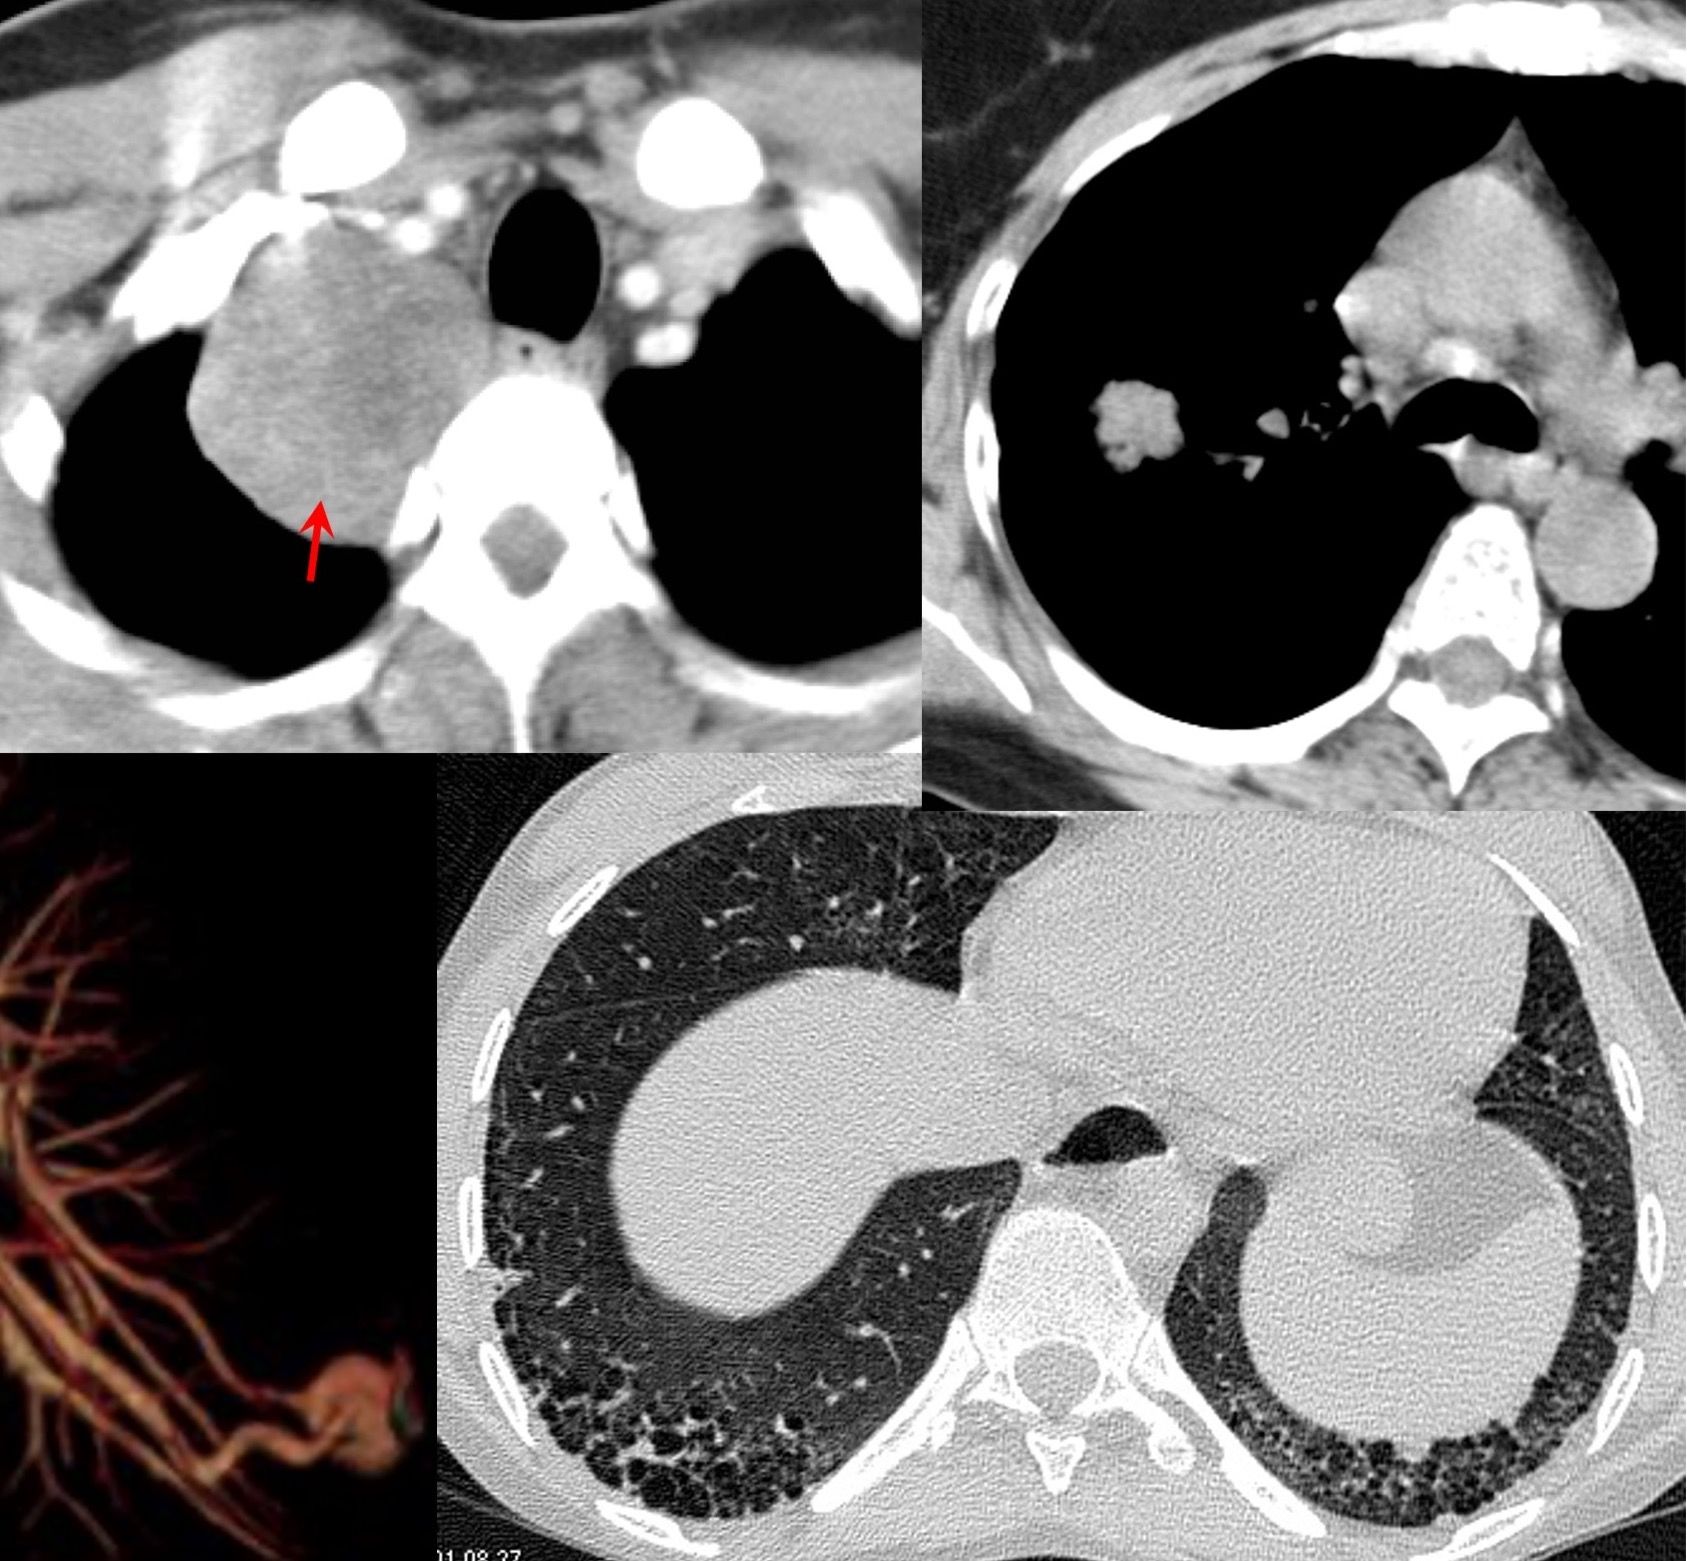

37-years old with gradually progressive dyspnea.

Upper lobe reticular opacities with volume loss, extending below tracheal bifurcation, small left pneumothorax.

CT images show classic findings of pleuroparenchymal fibroelastosis (PPFE), with no other associated etiology, hence idiopathic - iPFFE.